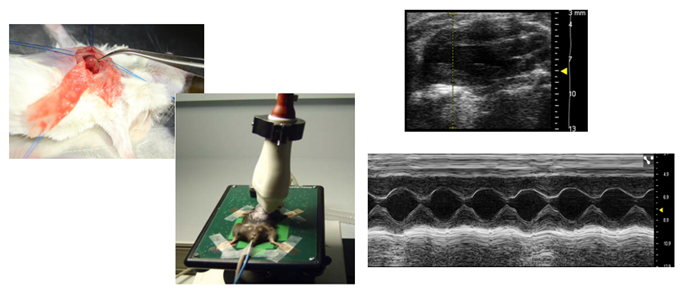

- Indukcja zawału serca

- Transplantacja biodrukowanych tkanek

- Monitoring efektu za pomocą echokardiografii